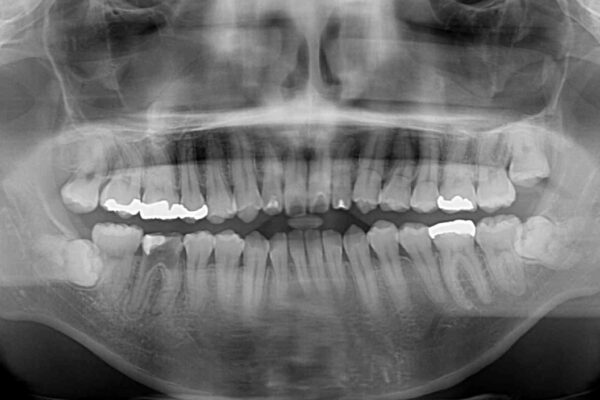

治療前

• 口元の突出感を改善!目立ちにくいワイヤー矯正で自信を持てる自然な横顔に 治療前画像

精密検査の結果、上下左右の小臼歯4本を抜歯し、そのスペースに前歯を後方へ移動させる矯正治療をご提案しました。